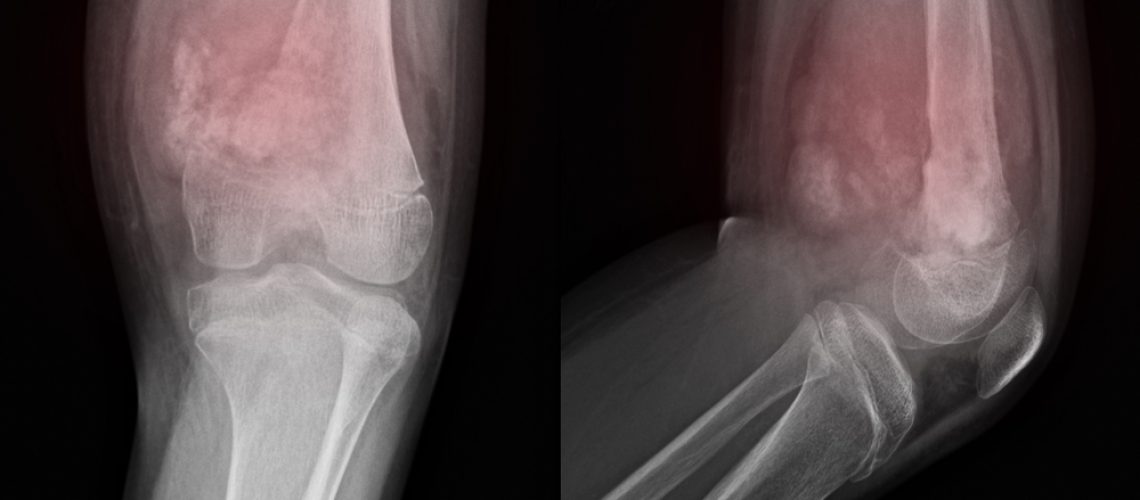

Osteossarcoma é um tipo de tumor que surge inicialmente nas células dos ossos. Ele pode começar em qualquer osso do corpo, mas é muito mais recorrente nos seguintes:

- osso superior do braço, na região próxima ao ombro;

- fêmur, nas proximidades do joelho;

- tíbia, também próximo ao joelho.